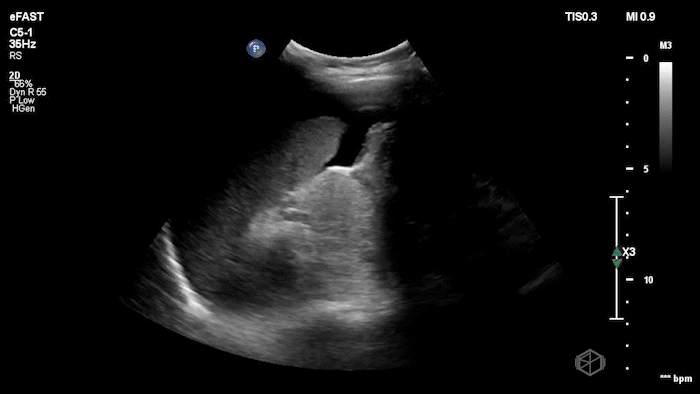

Dr.’s Konner and Maher scanned the patient and saw the following:

Initially it appears as though there is anechoic material above the liver and it does seem to make sharp angles. However, Dr. Konner and Dr. Maher utilized color doppler to evaluate the area and noted that it was simply the inferior vena cava. The patient ultimately had a CT scan that demonstrated no emergent findings.

Diagnosis: Potential false positive FAST - Inferior Vena Cava as a mimic of Free Fluid.

• Vessels can mimic free fluid. The IVC and other vascular structures sit right where we look for RUQ fluid and may appear anechoic in a single still frame. Use color doppler when not sure, free fluid will most commonly be at the caudal liver tip, and rarely just above the spine where the IVC sits.